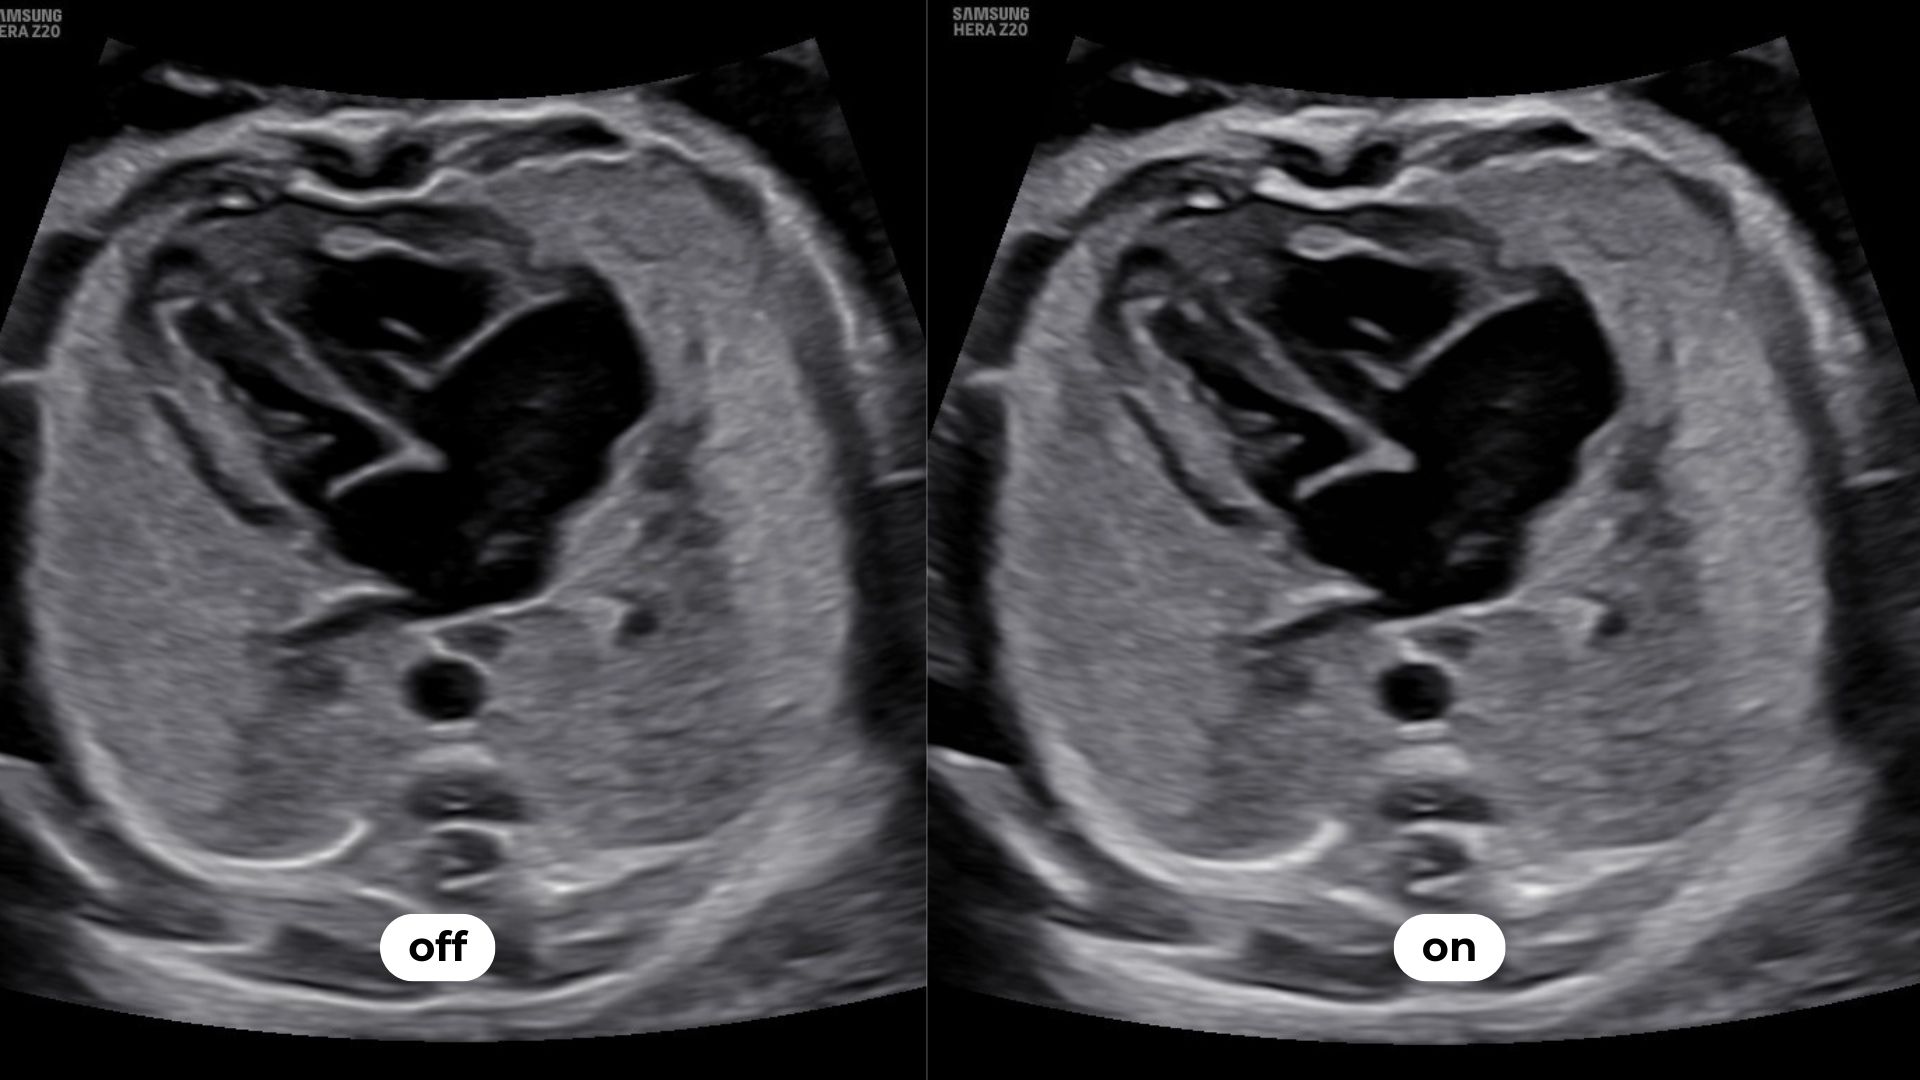

Luminant™ est un algorithme de différenciation structurelle qui transforme les contours d’une image 2D et améliore l’analyse des structures, comme pour le cœur ou le cerveau fœtal.